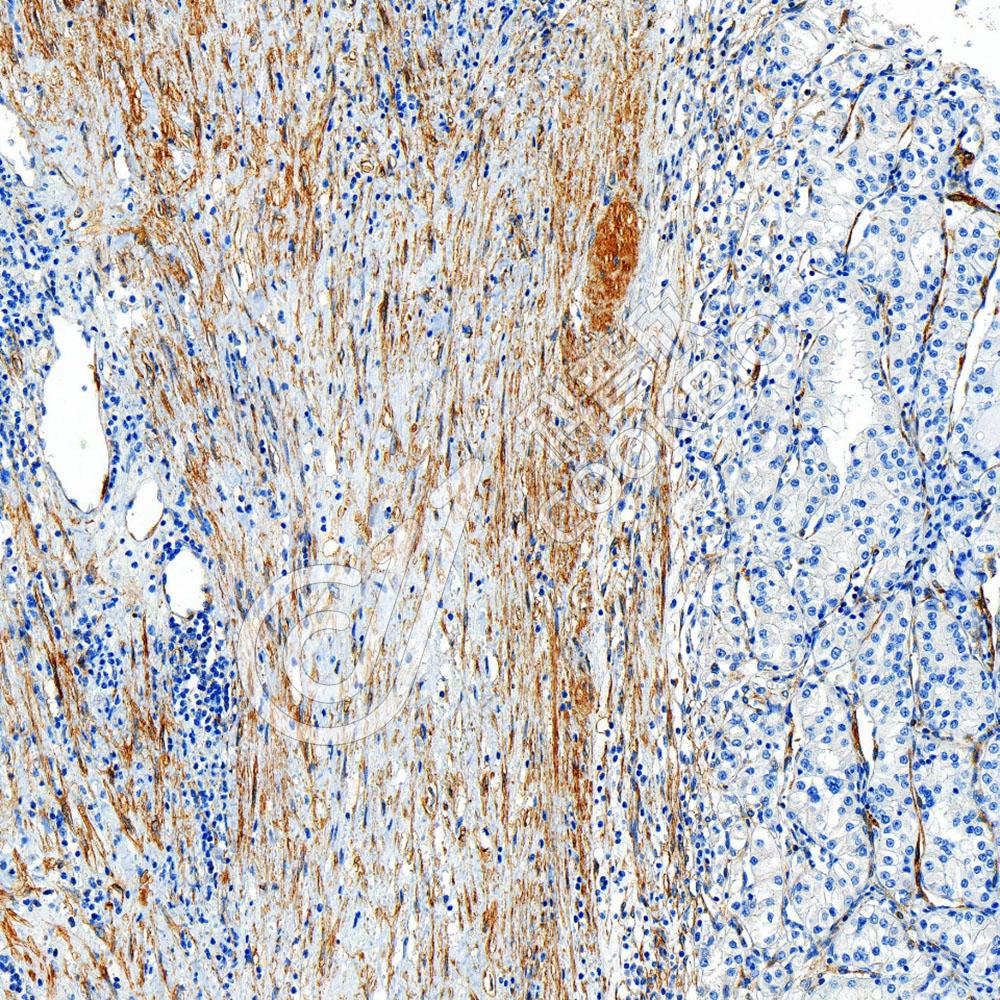

IHC检测Vinculin蛋白(货号 K5450204).

样品: 小鼠心, 4%多聚甲醛 (货号KSG1101) 固定12-24小时.

抗原修复: 柠檬酸抗原修复液(干粉, pH 6.0) (KSG1201), 高压锅均匀喷气计时2分钟.

—抗: 1: 1500稀释, 4℃ 孵育过夜.

二抗: S-vision免疫组化多聚二抗(山羊抗小鼠), 即用型(货号KB3903), 室温孵育20分钟.

样品: 小鼠睾丸, 4%多聚甲醛 (货号KSG1101) 固定12-24小时.

样品: 人肾癌, 4%多聚甲醛 (货号KSG1101) 固定12-24小时.